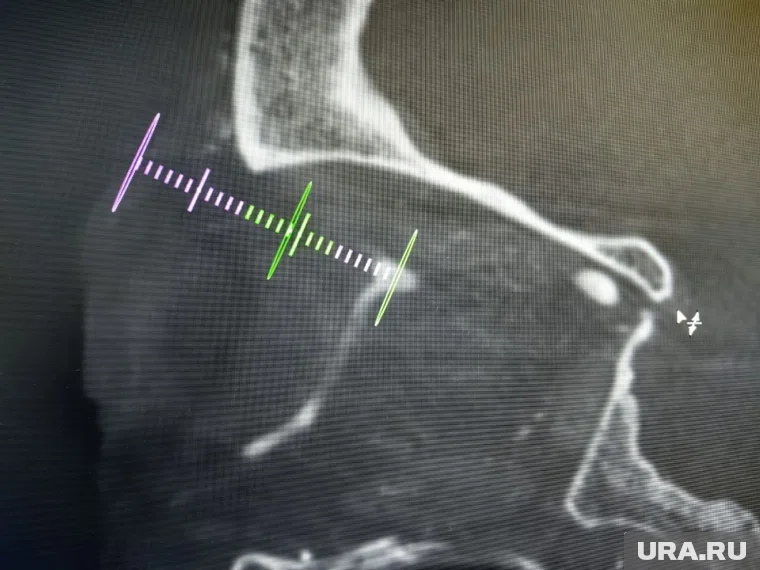

В травматологической больнице Сургута (ХМАО) впервые провели сложную операцию на сосудах головного мозга через глазницу. Они обнаружили у пациентки редкую патологию, которая мешала работе зрительного нерва, поэтому у женщины опух глаз, сообщили в медучреждении.

«71-летнюю женщину госпитализировали в травматологическую больницу с ушибом бедра. В стационаре врачи заметили воспаленный, отекший глаз и выпяченное глазное яблоко и распознали редкую аномалию — артериовенозную фистулу сосуда головного мозга. Из-за анатомических особенностей пациентки проход инструмента через лицевую вену или глубокие вены основания черепа был невозможен, поэтому впервые в своей клинической практике применили трансорбитальный доступ», — сообщил telegram-канал Сургутской травматологической больницы.

Обычно такие операции делают через вену на шее, но такой способ не подошел из-за особенностей строения сосудов у пациентки. Операция проходила рядом с важными нервами и сосудами глаза, поэтому врачи использовали специальное оборудование для навигации.

Во время вмешательства врачи перекрыли патологический сосуд с помощью специальных микроспиралей и материалов, чтобы кровь шла по правильному пути. После операции пациентку наблюдал нейрохирург вместе с реабилитологами. Женщина быстро пошла на поправку: у нее прошли отеки, а глаз вернулся в нормальное положение. По данным больницы, это первый случай в регионе, когда для лечения такой сосудистой патологии головного мозга использовали доступ именно через глазницу.